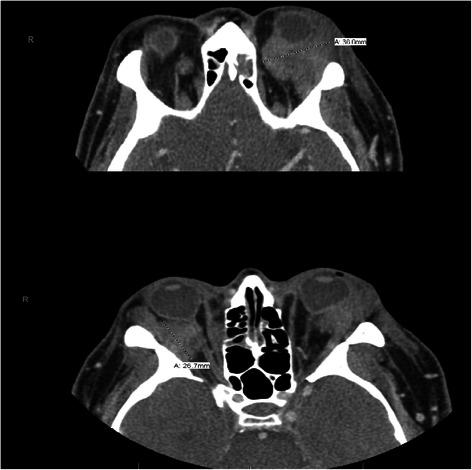

We present an unusual case of retro-orbital myeloid sarcoma as an initial presentation of acute myeloid leukemia in a 43-year-old Caucasian man, with rearrangement of chromosome 11q23 involving the MLL gene.

我们报告一例不寻常的眶后髓系肉瘤病例,该病例为一名43岁白种男性急性髓系白血病的初始表现,伴有涉及MLL基因的11q23染色体重排。